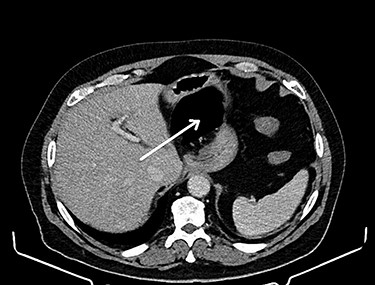

CT of the abdomen is considered the gold standard of the diagnosis of the internal hernia through the foramen of Winslow. The most prominent feature is the presence of intestinal loops between the inferior vena cava and portal vein [4] (see Fig. 1). Another classic feature is the presence of distended intestinal loops posterior to the stomach, which is displaced along with first and second part of the duodenum to the left [5] (see Fig. 2).

Intestinal loops (arrow) between the inferior vena cava and portal vein.